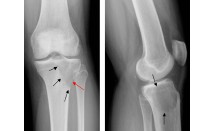

Fracture de Segond